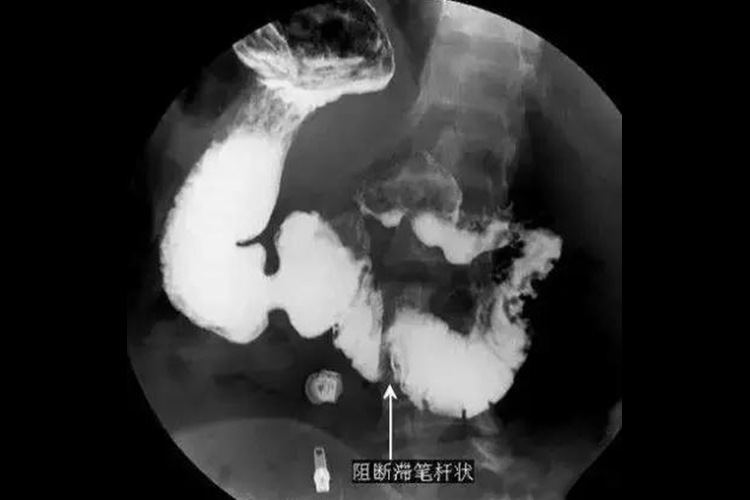

十二指肠溃疡:90%位于球部,龛影是十二指肠溃疡的直接征象,由于十二指肠球腔小壁薄,发生溃疡后容易变形,表现为“山”字形、花瓣形或管状等,间接X线征象有激惹现象,表现为钡剂不在球部停留,迅速通过。